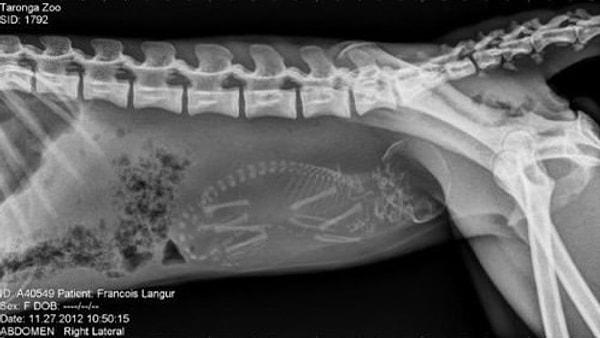

12. Обезьяна